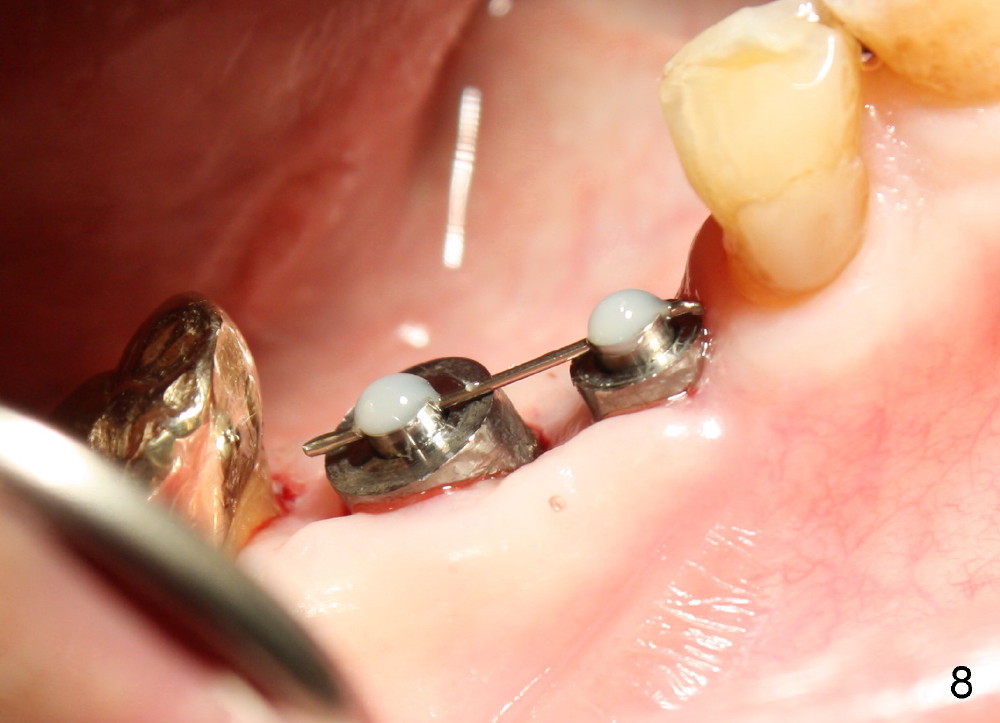

One month after implant placement at the sites of #29,30, the former is found loose (Fig.1,2). It is placed higher than #30. Three weeks later, PA is retaken to confirm that there is space apical to the implant at #29 (Fig.3 double arrows) and that there is distance from the mental loop (yellow dashed line). After infiltration anesthesia, the implant is torqued down initially (compare Fig.4,5) and more (Fig.6,7). To prevent re-loosening, the two implants are splinted (Fig.8).